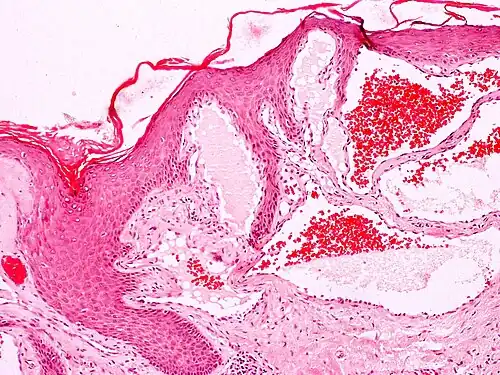

Angiokeratomas characteristically have large dilated blood vessels in the superficial dermis and hyperkeratosis (overlying the dilated vessels).

Scrotal angiokeratoma; visible large dilated blood vessels and hyperkeratosis -